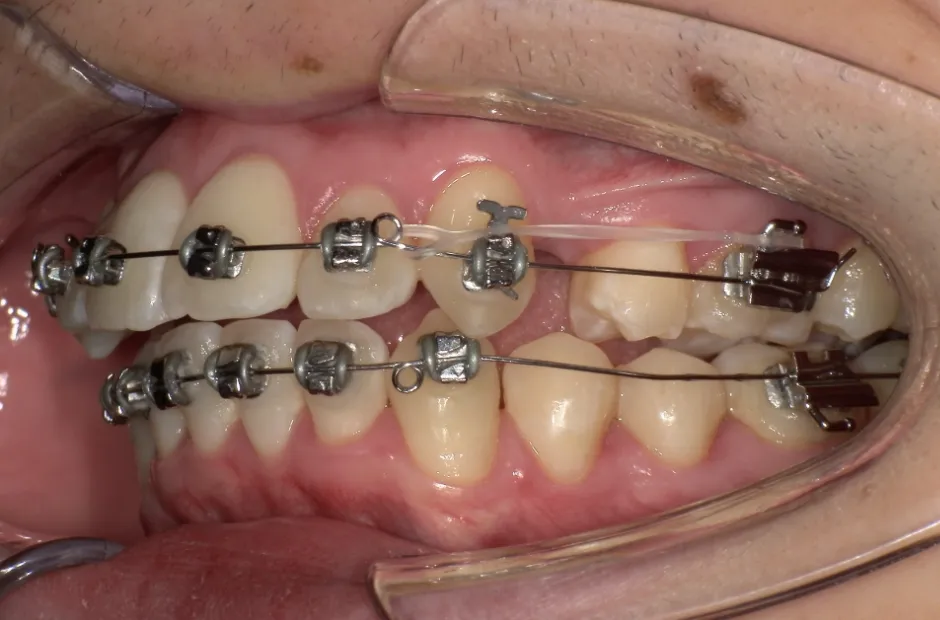

治療症例

ブラケット矯正

前歯部反対咬合

| 診断名・主訴 | 前歯部反対咬合 |

|---|---|

| 年齢・性別 | 14歳・男性 |

| 治療期間・回数 | 1年2か月 |

| 治療に用いた主な装置 | ブラケット矯正 |

| 抜歯部位 | なし |

| 治療費 | 60万円(税抜) |

| リスク・副作用 | 装置による違和感・疼痛・歯肉退縮・歯根吸収・虫歯のリスクなど |

治療中